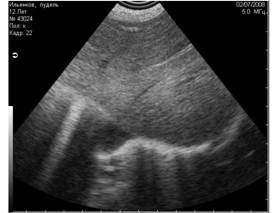

![]() |

Рис. 11. Истинные тени, испускаемые скелетными структурами плода шелти на 36 день беременности. Первичными очагами минерализации являются череп и таз плода. На этом снимке мы видим две тени, испускаемые этими структурами. |

Рис. 12. Истинные эхоакустические тени, испускаемые уплотнёнными стенками сосудов при гепатозе (фиброзе). |